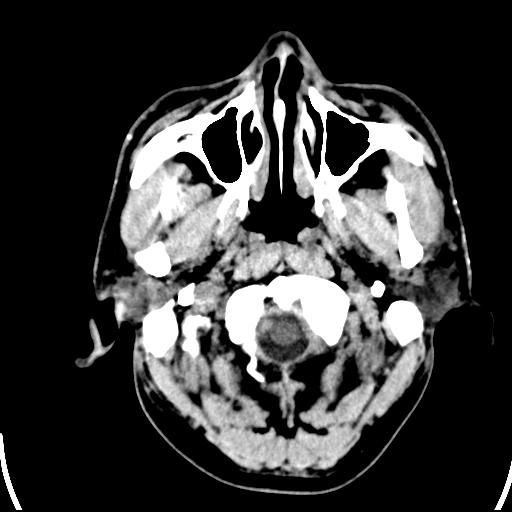

标题: CT25435:头皮下高密度影???

头皮下高密度结节影???临床上在老年男性比较常见。大家看看是什么?成因是? 本例患者,男性,51岁。外伤来诊。无染发史及发根植入史。

皮下钙化点

没见过,可能为毛囊钙化。

考虑钙化。